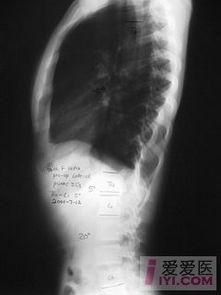

那么,脊柱凹凸图到底有什么好处呢?首先,它可以帮助你更好地了解自己的脊柱状况。通过观察脊柱的凹凸程度,你可以判断自己的脊柱是否健康,是否存在弯曲等问题。